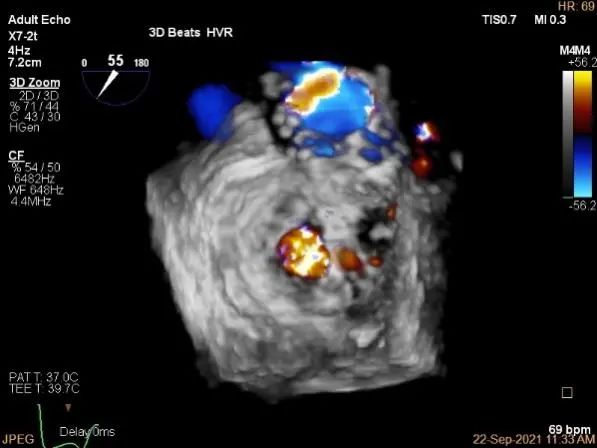

3D-color,返流重度,3+级

三维评估两个夹子位置

3D-color再次确定未见残余分流

3D:P1区脱垂并腱索断裂,Width:11.4mm

3D-color:重度MR,4级

3d确认夹子位置在P1区

3d-color确认残余分流情况